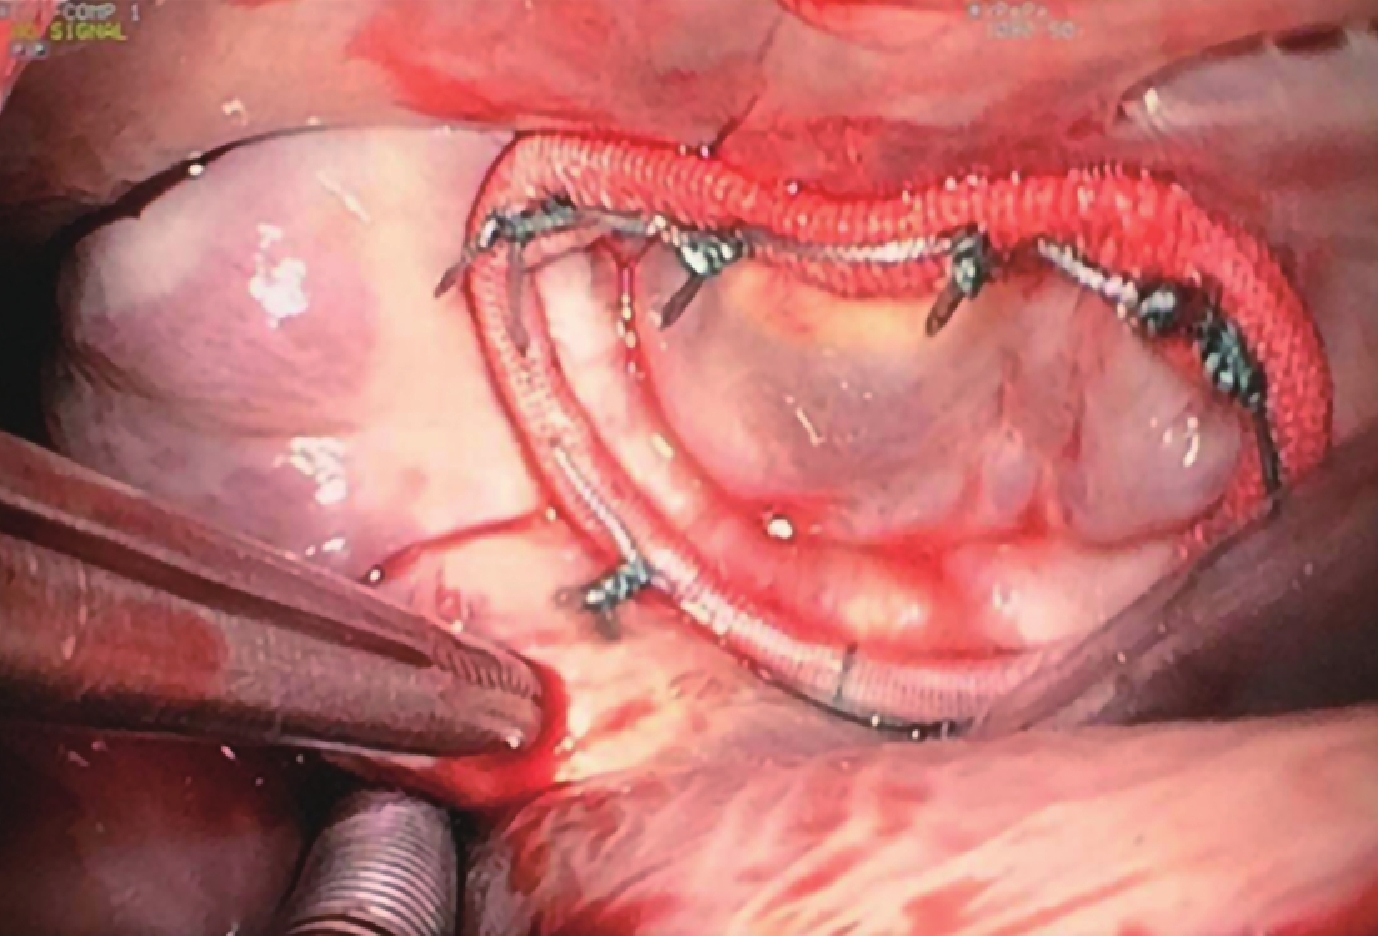

于右側膈神經前 2~3 cm 處平行右側膈神經作心包切口。阻斷上、下腔靜脈后,從房間隔或房間溝入路,縫制房間隔牽引線充分顯露。在房壁切口上縫合兩針牽引線,并牽拉暴露二尖瓣;經房間隔切口放置左房引流減壓管,如部分瓣環暴露不清,可以在瓣葉上縫合牽引線調整角度,可在顯示屏上完全得到整個瓣環圖像,探查二尖瓣情況;見圖 4。再次確定腱索斷裂的具體位置與測量人工腱索長度。于斷裂處的乳頭肌測量點下 3 mm 位置穿過乳頭肌,于對側再次穿墊片打結,將第一級 loop 縫合于乳頭肌上;見圖 5。第二級 loop 穿過第一級 loop 人工腱索環,縫合在脫垂的瓣葉光滑面和粗糙面交界。第二級 loop 的長度根據計算腱索長度減去第一級 loop 的長度,重建二尖瓣瓣葉對合緣和乳頭肌之間的連接,采用推結器進行打結。重建完一個腱索后進行壓力打水試驗,探查二尖瓣關閉情況,根據對合程度可以再次調整第二級 loop 長度,確認第二級 loop 長度。所有人工腱索重建后再次壓力注水試驗,再次確認二尖瓣對合良好,無明顯反流;見圖 6。所有病例在測量瓣環后分別置入相應大小的成形環(Medtronic CG Future 638R);見圖 7。合并三尖瓣中度及以上關閉不全的患者均同期行三尖瓣成形術。若合并心房顫動,則同期行改良迷宮射頻消融及左心耳縫扎手術。待心臟復跳血流動力學穩定后行 TEE,觀察二尖瓣閉合情況。